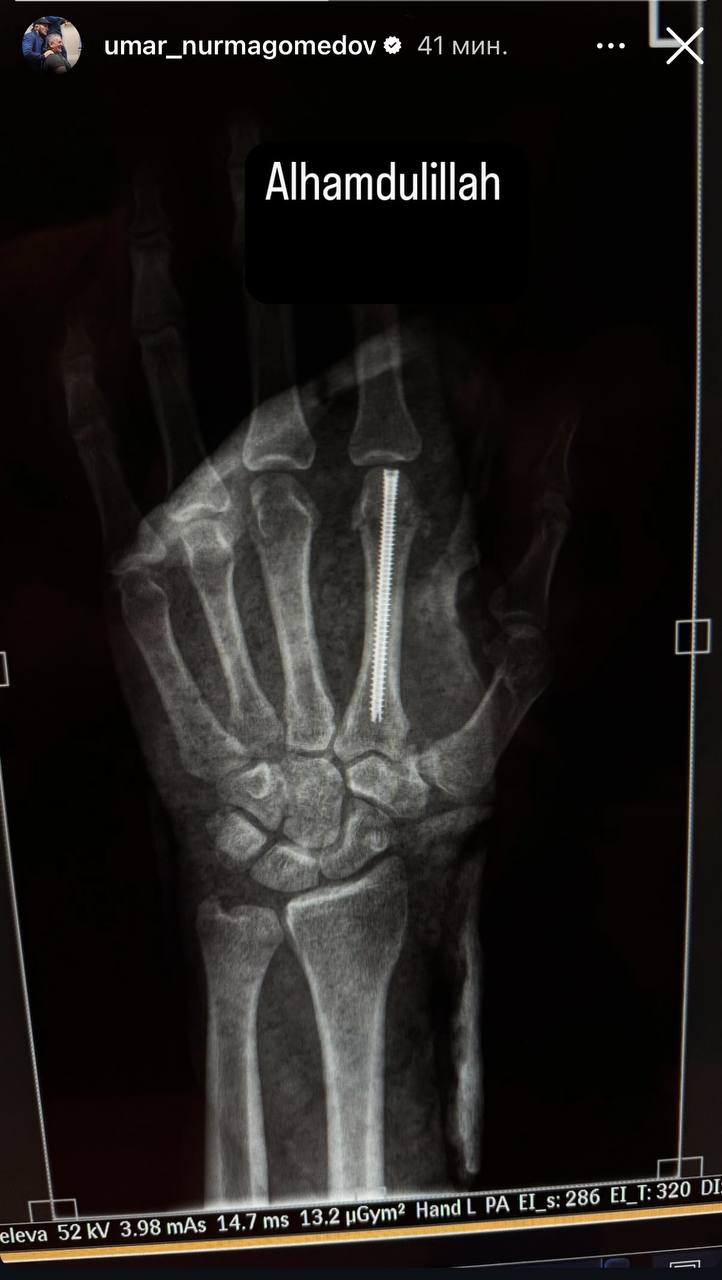

Умар Нурмагомедов показал рентген руки, сломанной в бою с Двалишвили

Sport.ru / ММА. Российский боец смешанных единоборств Умар Нурмагоемдов опубликовал в своих социальных сетях рентгеновский снимок своей руки, которую он сломал в поединке с Мерабом Двалишвили.

Напомним, бой между Нурмагомедовым и Двалишвили состоялся на турнире UFC 311. Умар повредил руку уже в первом раунде. По итогам боя, который продлился все пять раундов, судьи единогласно отдали победу Мерабу Двалишвили.

Двлишвили успешно защитил титул в легчайшем весе UFC, а Умар Нурмагомедов потерпел первое поражение в карьере.